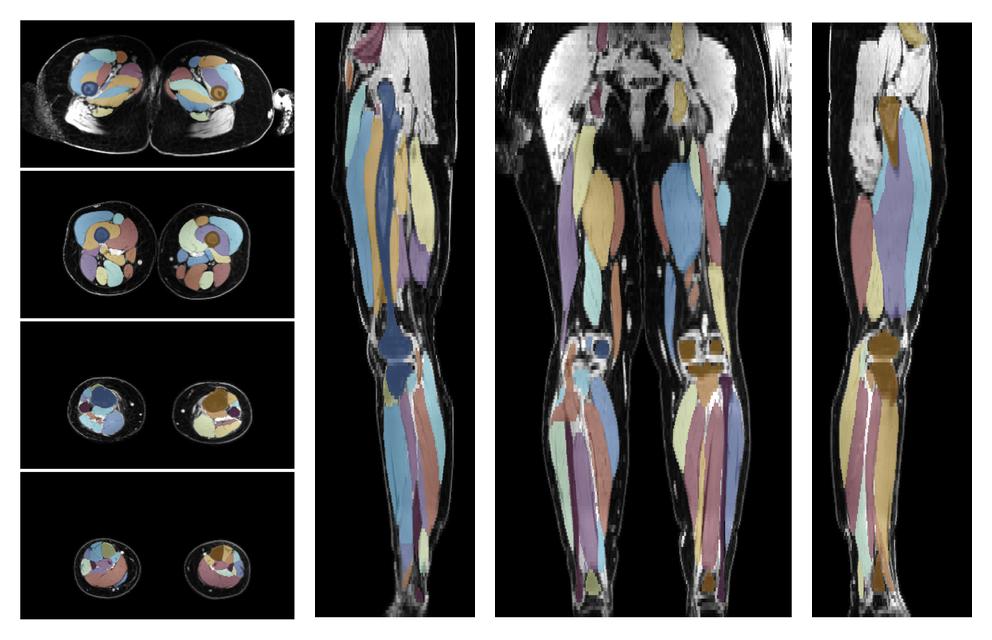

Muscle segmentation

Convolution neural network based (UNET) fiber automated muscle segmentation, for information look here».

• 3D volume render of automated muscle segmentation.

3D render of automated muscle segmentation labels generated using a CNN UNET.

• Automated muscle and bone segmentation.

Overlay of automated muscle segmentation labels on dixon water image.